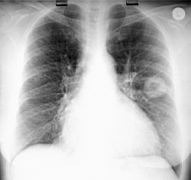

This patient has both a pulmonary abscess and an empyema at the same time! |

Lateral view, same patient |

Cavitating mass in L lung -- for fun, let's poke this with a needle and see if we catch TB! |